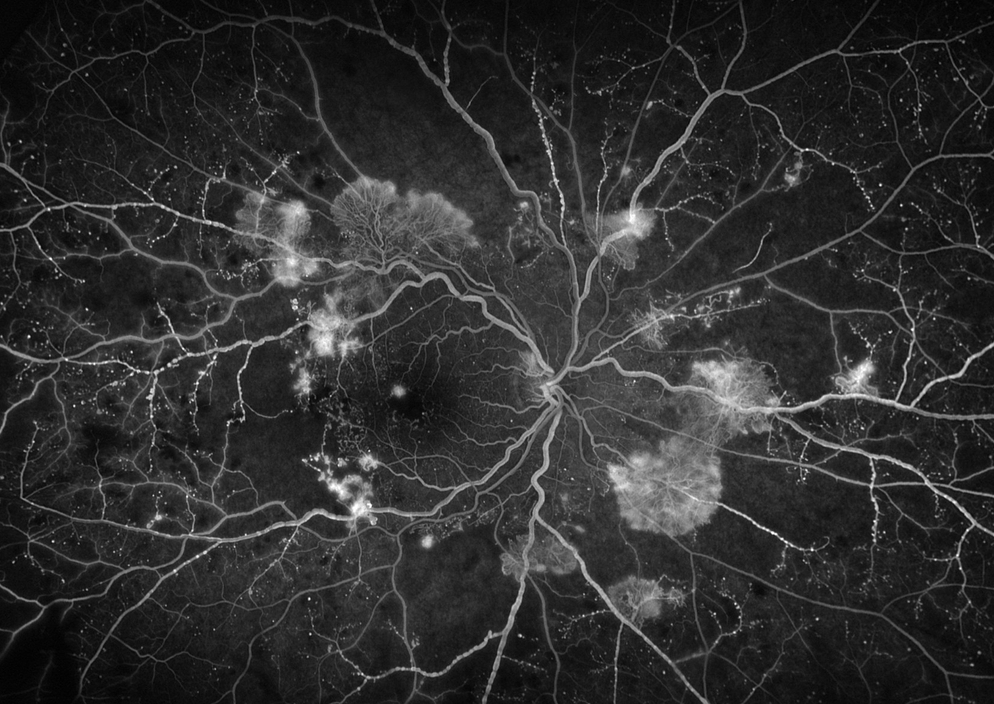

Abbildung 1: Patient mit proliferativer DR, multiplen Proliferationen & Minderperfusion

Abbildung 2: Patient mit proliferativer DR, OCTA (A) mit B-Scan (b) und FLA (C)

Abbildung 3: Nicht-durchblutete Areale (gelb) in zunehmenden DR Stadien (von links nach rechts)

Abbildung 4: Farbfotographie (links) & OCTA (rechts) desselben Patienten

Die Fluoreszenzangiographie (FLA) ist der Goldstandard zur Beurteilung der Netzhautgefäße: Ein Farbstoff wird intravenös injiziert, die Verteilung über ~10 Minuten fotografiert. So lassen sich Gefäßneubildungen, Undichtigkeiten und Areale ohne Durchblutung auch in der Peripherie sicher darstellen. Nachteile sind die Invasivität, der Zeitaufwand und seltene Nebenwirkungen.

Optische Kohärenztomographie Angiographie

Die OCT-Angiographie (OCTA) misst Blutfluss ohne Farbstoff, indem die gleiche Stelle mehrfach gescannt und Bewegung im Gefäßlumen detektiert wird. Sie ist schnell, nicht-invasiv und schichtet die Netzhaut in Plexus auf. Limitationen: kleineres Sichtfeld als FLA und mögliche Artefakte bei langen Scans oder Augenbewegungen.

Errungenschaften der Universitätsklinik für Augenheilkunde & Optometrie Wien

Gemeinsam mit der MedUni Wien wurde ein Widefield-OCTA-Prototyp entwickelt (≈15 s Aufnahme, Bilddurchmesser ~18 mm). Dieses System erlaubt eine rasche, hochqualitative, nicht-invasive Gefäßdarstellung der gesamten Netzhaut, inklusive Peripherie. Darauf aufbauend konnten mehrere klinische Projekte erfolgreich umgesetzt werden.

Detektion von Proliferationen

Für die Diagnose der proliferativen diabetischen Retinopathie ist das Erkennen von Neovaskularisationen entscheidend. Mit der Widefield-OCTA gelang in 95 % der Fälle die richtige Diagnosestellung; kleine Gefäßanomalien lassen sich oft detailreicher zeigen als mit FLA. Damit eignet sich die Methode besonders für Screening und Verlauf.

Kombination mit Fundusfotographie

Die Verknüpfung von Farbfundusbildern mit Widefield- OCTA erlaubt eine mehrschichtige Analyse: Struktur (Foto) und Perfusion (OCTA) werden deckungsgleich beurteilt. Das erleichtert das Mapping von Läsionen, das Monitoring unter Therapie und die Kommunikation mit Patient:innen.

Nicht-durchblutete Areale

Mit Fortschritt der Erkrankung nehmen Nichtperfusionszonen zu und bedrohen die Netzhautversorgung. Widefield-OCTA macht diese Areale in allen Stadien sichtbar und quantifizierbar. So können Risikoabschätzungen und Therapieanpassungen (z. B. Panretinale Laserung) gezielter erfolgen.